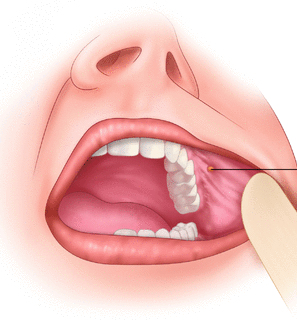

Vestibule

Gingiva

what’s the anatomical term for gums?

Opening to parotid duct